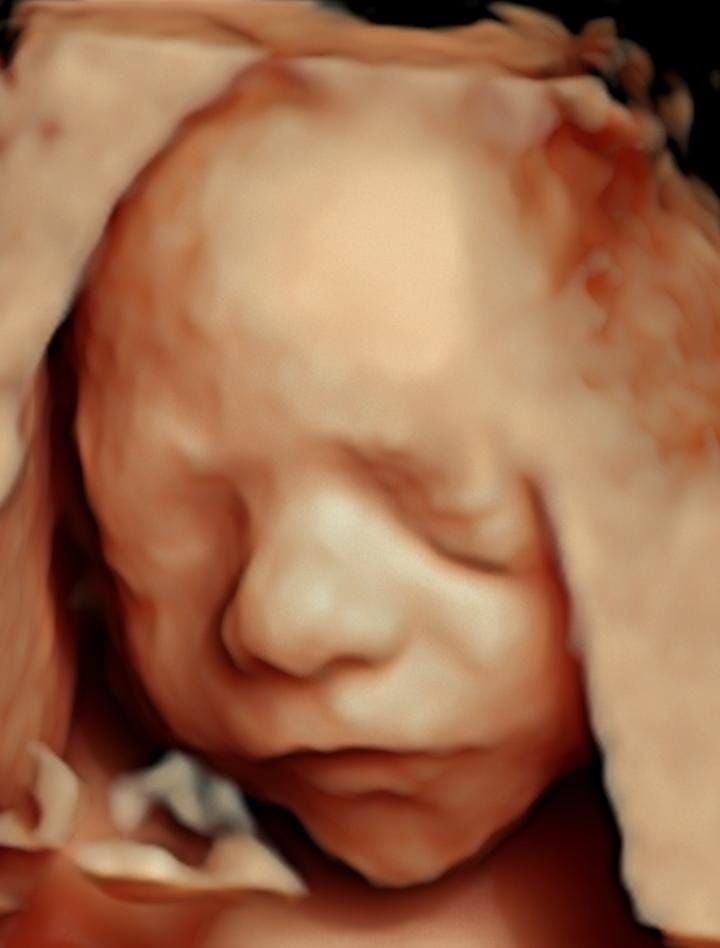

Realizamos ultrasonidos 3D y 4D obstétricos, donde puedes ver en tiempo real a tu bebe así como la evaluación Doppler para determinar el bienestar fetal.

• Ultrasonido 3D

$2,000

• Ultrasonido 4D